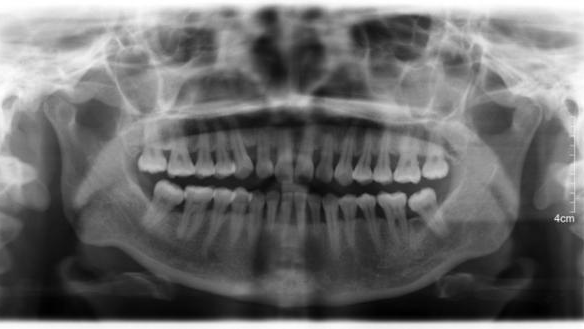

牙周炎口内照

牙周炎X线片

牙周病会导致牙龈和牙槽骨的退缩,这是牙周病进展的结果。当牙龈和骨头萎缩后,牙齿之间的支撑减弱,牙缝也会因此变得更明显。

虽然牙周治疗能够控制和改善炎症,但对已经发生的牙龈萎缩却难以逆转。因此,牙周治疗后,你可能会发现牙缝“变大”了。